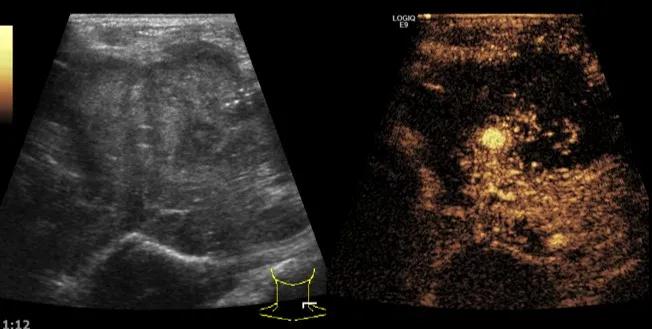

第三例是甲状腺癌患者,双侧甲状腺癌切除术后、碘治疗后一年余效果欠佳,超声显示左颈3区3枚低回声结节,穿刺示甲状腺乳头状癌转移。患者不愿意手术,希望采取局部治疗。对病灶进行液体隔离后采取热消融术,由于淋巴结较小,热消融一分钟左右完全灭活,术后增强影像显示没有脏器充填。

(病例3图例)